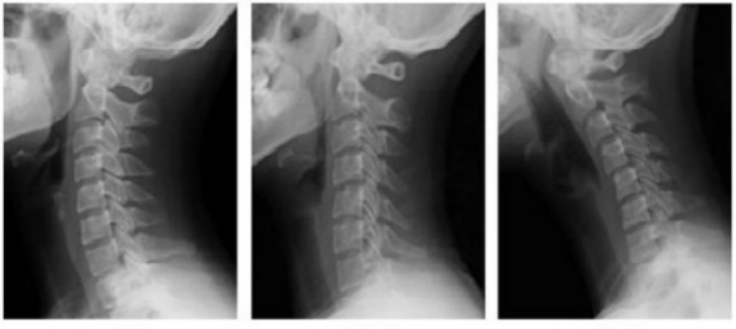

거북목 증후군이라는 증상이 말 그대로 목을 내밀고 있는 증상인데, Xray를 통해서도 쉽게 확인이 가능하다.

아래 X ray 결과 왼쪽이 정상 사람의 X ray 결과이다. 약간 뒤쪽으로 뼈가 휘어서 활처럼 모습을 보이고 있다.

이게 정상이다.

거북목이 되기전 일자목의 상태를 거치는데 가운데 x ray 그림의 결과가 일자목이다.

거북목 초기증상으로 볼 수 있을정도로, 관리가 필요한 상태이다.

거북목의 진행상태를 X ray를 통해 확인 했으면, 이제 이 증상을 완화하기 위한 조치 사항이 필요하다.